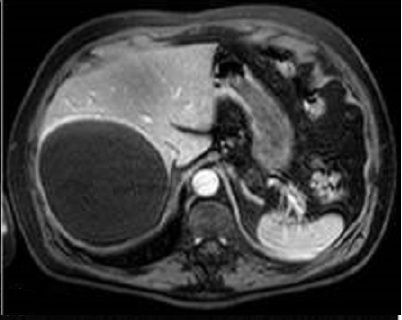

Aspect

radiologique d'une kyste biliaire simple du foie

.Lesion est tres hyperintense en T2 |

Et est hyposignal en T1 . N'a pas de

rehaussement apres injection de contrast

intraveineuse . Image TDM en coupe axiale . |